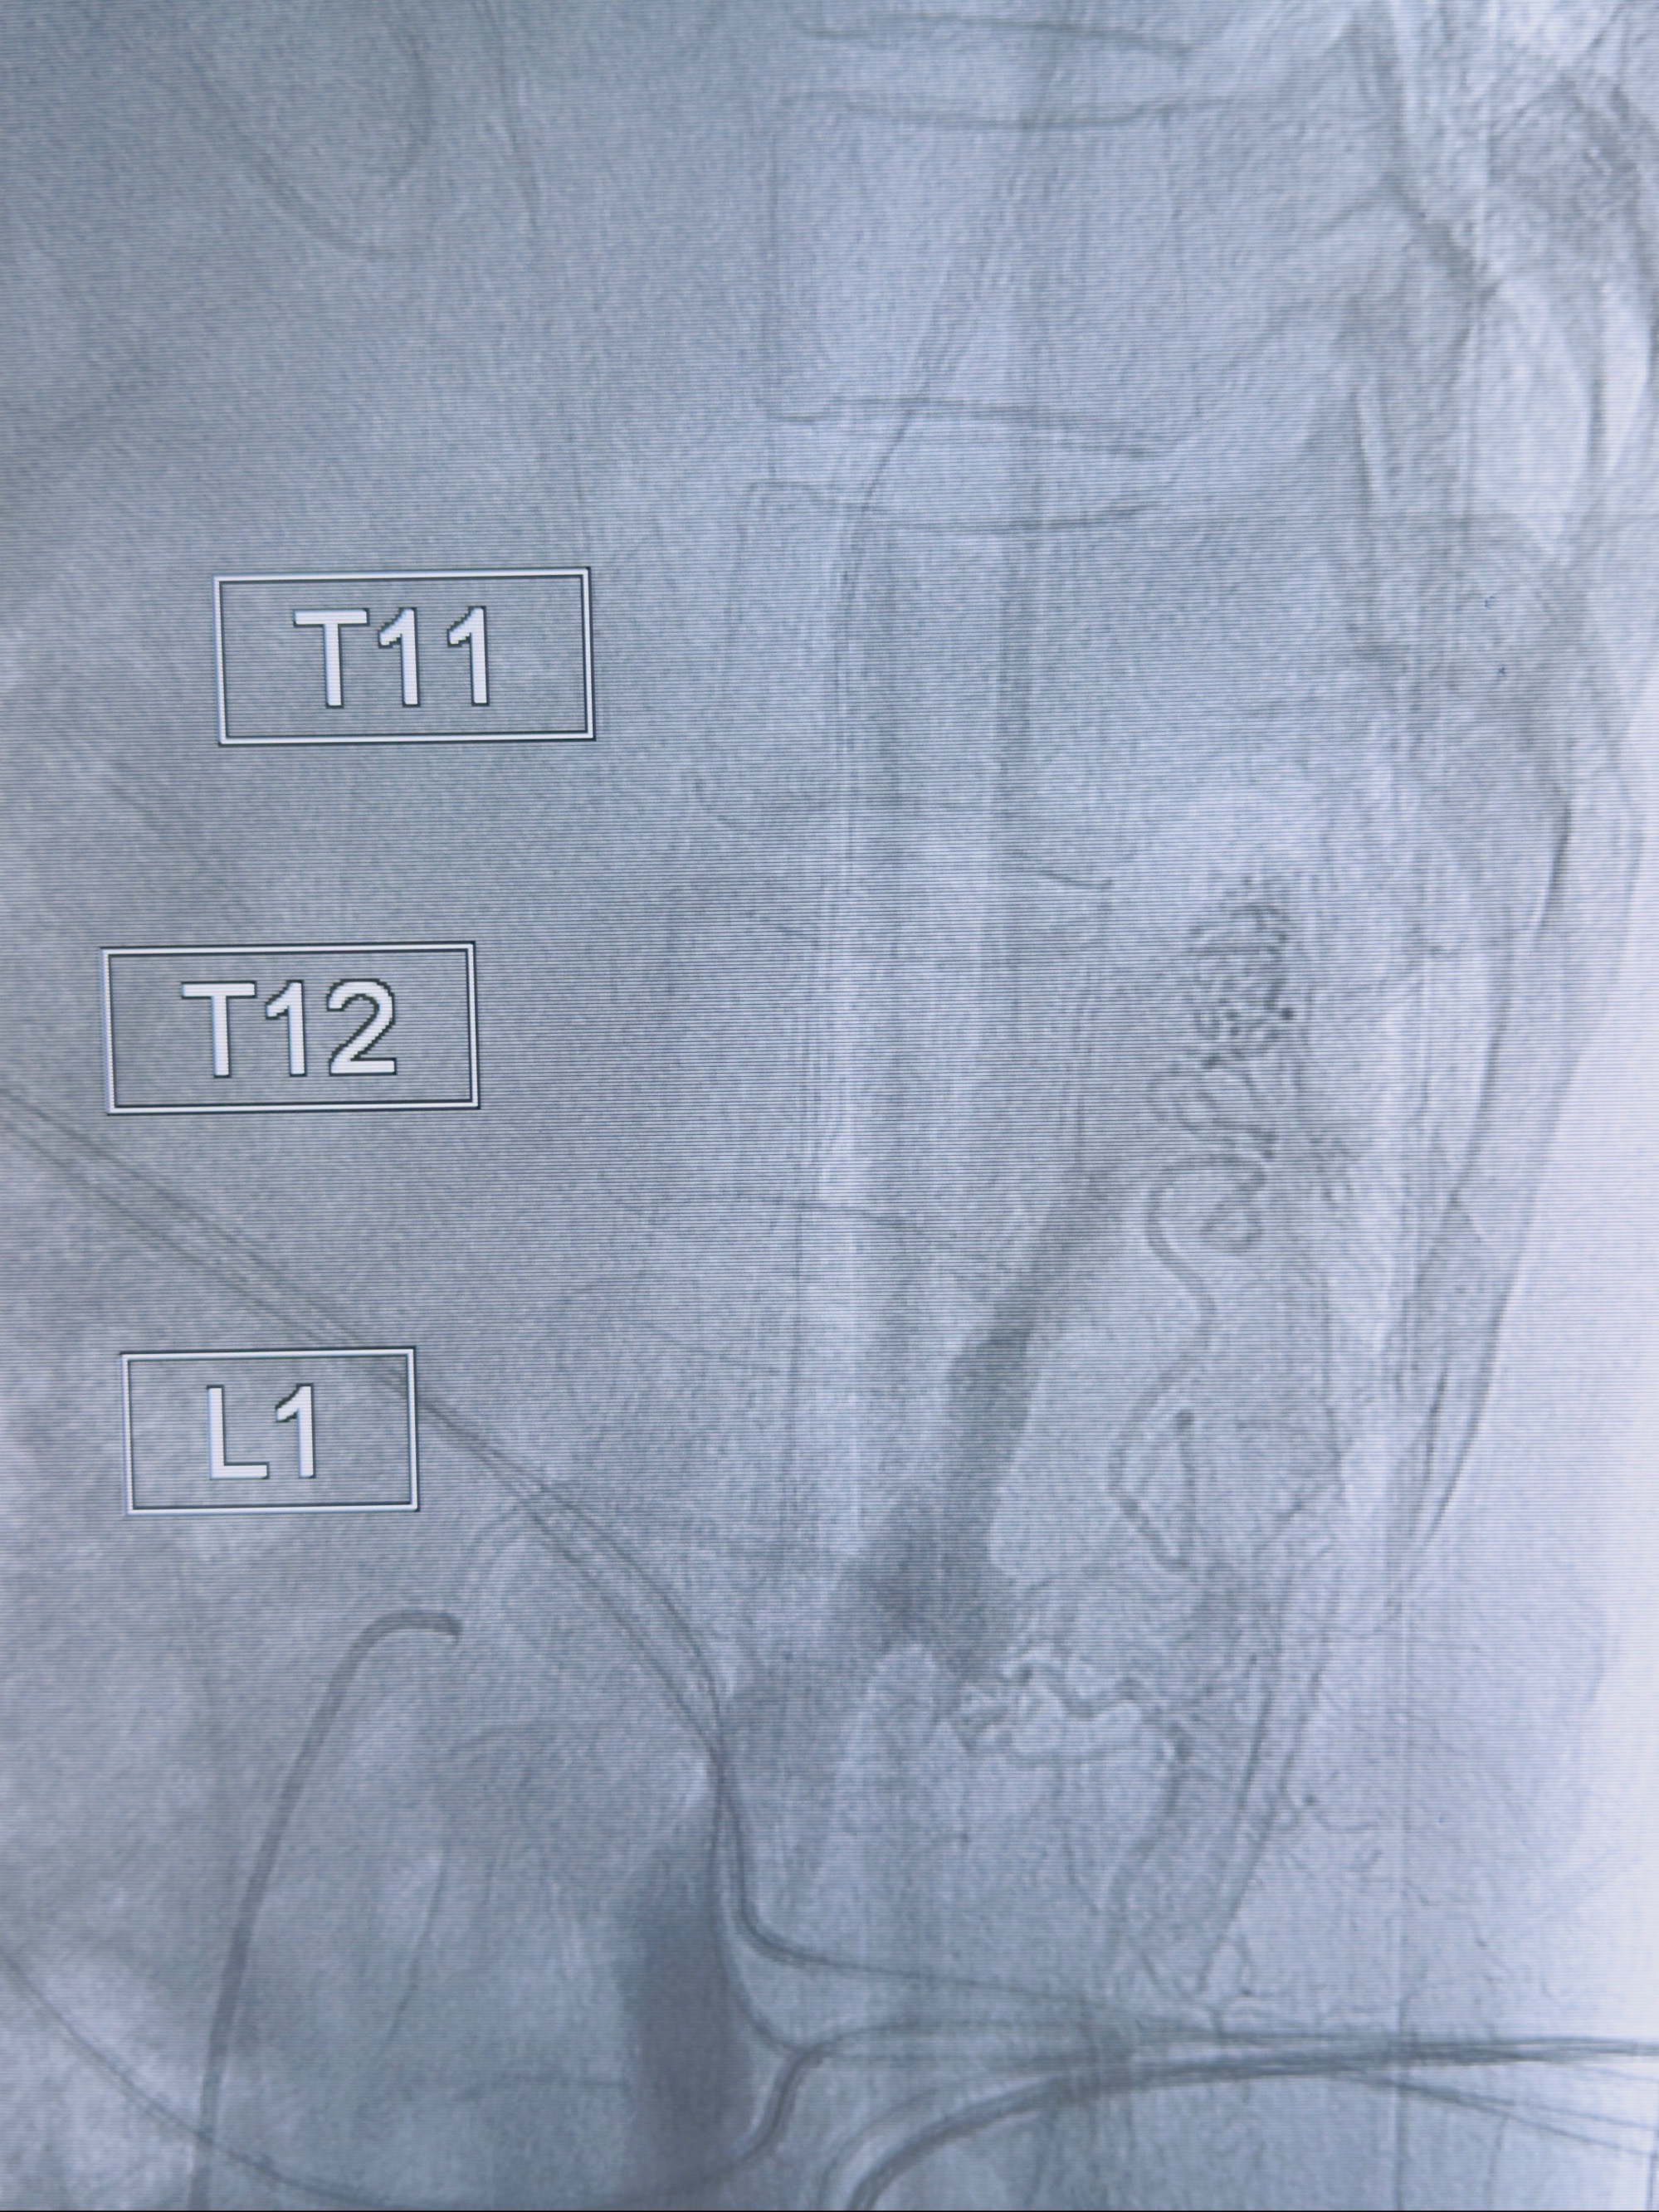

2023-10-13DSA:右侧L1水平硬脊膜动静脉瘘,供血动脉为右侧L1,附近动脉未见明确吻合供血,供血动脉处可见脊髓前动脉发出